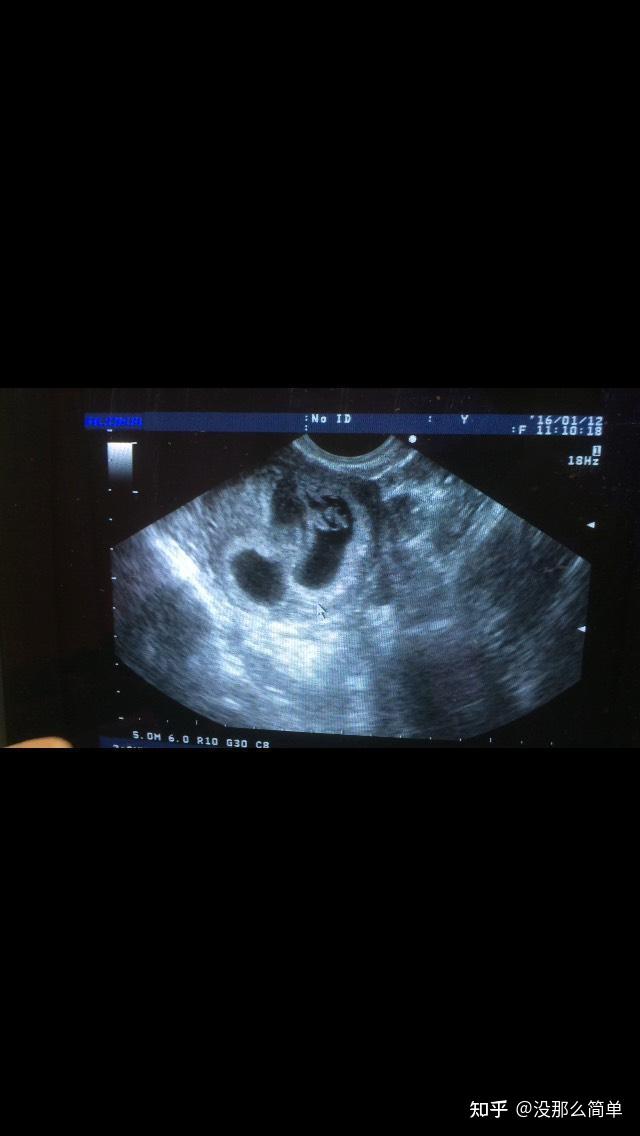

现在没有出血了,每天除了上班时间,下班回到家除了吃饭和洗手间,其余时间都卧床。b超提示宫腔还有很多积血(左上),一胎停止发育(左下),一胎暂时还可以(右)。心里觉得可能是出血压在停止发育那个宝宝那令他没养分供应而失去它的。